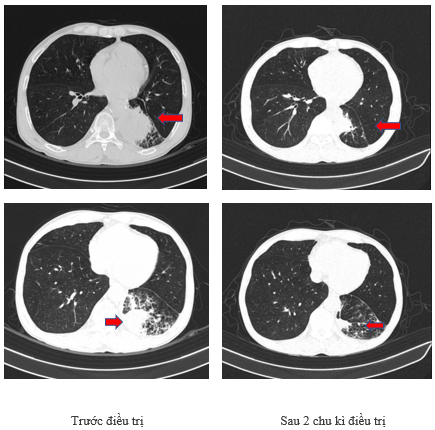

-        Chụp cắt lớp vi tính lồng ngực sau 2 chu kì điều trị: Phổi trái nhu mô thùy dưới có khối đặc kích thước 37x21mm nằm sát màng phổi, sau tiêm ngấm thuốc không đồng nhất. Phổi phải có vài nốt kính mờ nhỏ rải rác nằm sát màng phổi đường kính lớn nhất 4mm. Vài hạch nhỏ vùng trung thất trước và hạch nhóm IV cổ phải.

Hình 4: Hình ảnh chụp cắt lớp vi tính lồng ngực sau điều trị 2 chu kì: tổn thương u phổi giảm kích thước rõ rệt